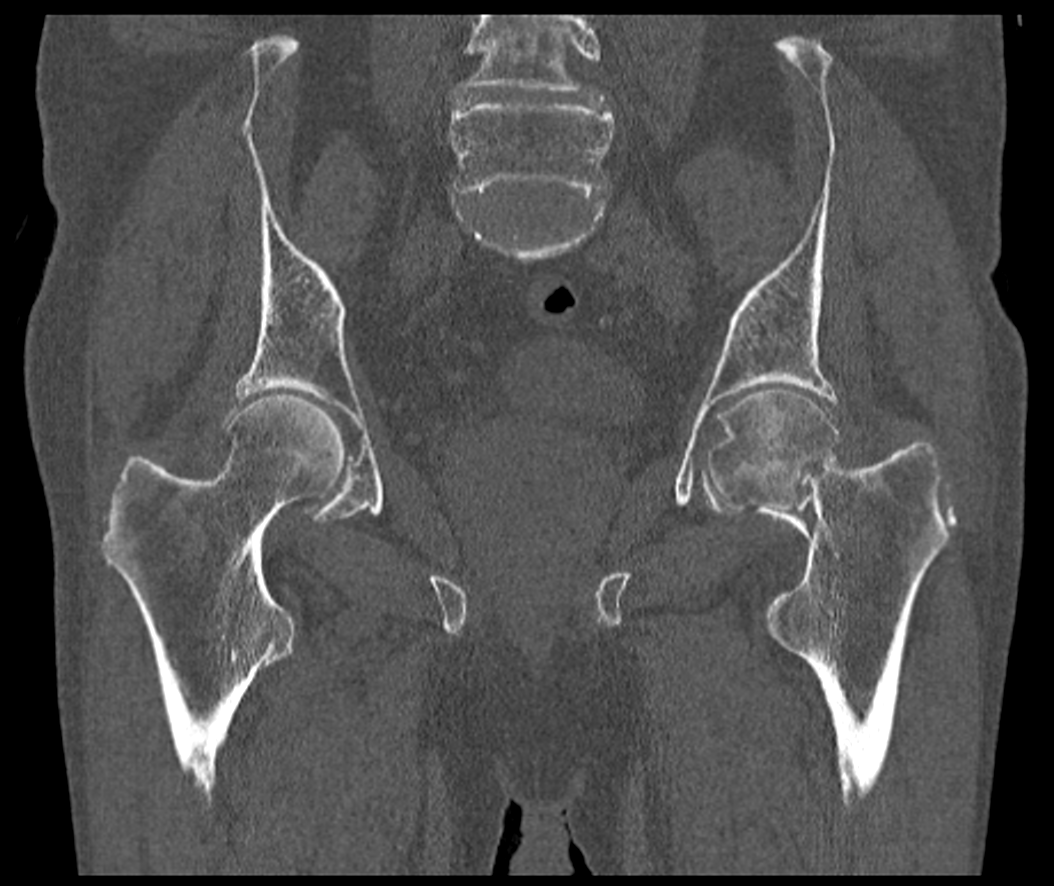

TC coronal simple